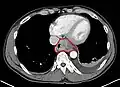

Esophageal cancer (lower part) as a result of Barrettʼs esophagus

Male predominance is particularly strong in this type of esophageal cancer, which occurs about 7 to 10 times more frequently in men.[25] This imbalance may be related to the characteristics and interactions of other known risk factors, including acid reflux and obesity.[25]